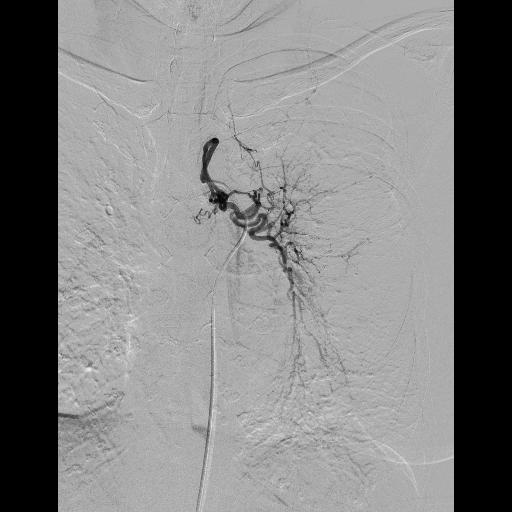

気管支動脈塞栓術(BAE)

陳旧性肺結核や抗酸菌症、慢性肺感染症、気管支拡張症等による血痰/喀血に対して、気管支動脈塞栓術(BAE)を行っています。

血痰/喀血が多い場合、止血剤や安静でも改善しない場合には、原因となる責任血管に塞栓物質を詰め、出血しないよう治療します。

前もって造影剤を使用したCT検査を行い、放射線科と協働して異常血管の3D再構築を行い異常血管の走行を確認します。

カテーテル検査/治療に卓越した循環器内科医と協働することで、安全かつ確実な治療を目指しています。